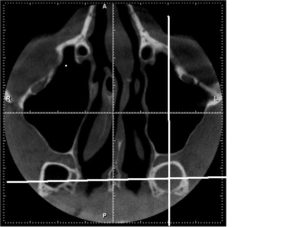

Единственными методами, которые наверняка могут определить сфеноидит, являются компьютерная томография (КТ) или магнитно-резонансная томография (МРТ) –

КТ — исследование пазухи с помощью рентгеновского излучения. КТ позволяет выявить аномалии синуса, степень поражения слизистой. При исследовании с помощью КТ определяется уровень гноя в пазухе.

Ещё более информативным методом диагностики является МРТ — она выявляет послойные поражения, которые могут быть не замечены на КТ.